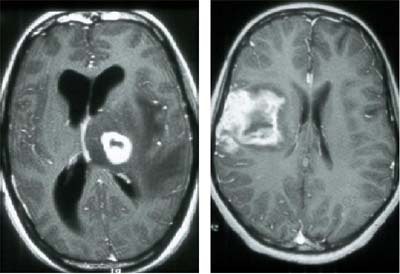

Toxoplasmosis is a protozoal intracellular parasite, which is probably the most common opportunisitic infection seen in AIDS patients. It is especially important to identify toxoplasmosis, because it responds well to treatment. CT and MR can be nonspecific, but the radiologist can sometimes find a telltale rim-enhancing abscess, particularly in the basal ganglia, and with cortical involvement.

| Toxoplasmosis infection in the brain of an HIV patient. Images courtesy of Dr. Peter Corr. |